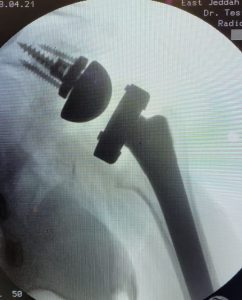

نجح فريق جراحة العظام بمستشفى شرق جدة من إجراء عملية معقدة لمواطن يبلغ السبعين من عمره حضر للمستشفى بعد شهرين و نصف إثر تعرضه لحادث مروري وخلال هذه الفترة كان يعاني من الام حادة. و أوضح رئيس قسم العظام الدكتور أحمد فهد عصر استشاري جراحة العظام و الأطراف العلوية ‏أن المريض تعرض لكسر مع خلع في رأس عظمة الكتف و كذلك كسر في عظمة اللوح المتصلة بالمفصل و تم تشخيصه من قبل طبيب مختص بإصابات الكتف و جرى تحويل المريض إلى مستشفى شرق جدة العام لوجود فريق متخصص لجراحات المفاصل العلويه و تم إيضاح حالته الصحية كاملة له و لذويه .

و بعد إجراء التشخيص الكامل تبين أنه يلزم تغيير مفصل مقلوب للكتف بواسطة مفصل مزود بأخرام يستعمل في حالات الكسور بربط منشأ الأوتار عليها بالإضافة إلى عمل ترقيع عظمي لعظمة اللوح بإستخدام بقايا الرأس المكسور و المتخشن ‏و إضافة إلى استعمال الحفار في مكان غير المكان المتعارف عليه لتثبيت القطعة المخصصة للوح في مكان أعلى لوجود عظم أقوى و أكثر كثافة ، و قد تم إجراء العملية التي استغرقت اربع ساعات و نصف بنجاح ، و تم متابعة المريض في العيادة و أصبح قادراً على رفع يده بشكل حركي ممتاز يمكنه من القيام بأعماله اليومية معتمداً على نفسه ، و كان الفريق الطبي المشارك مكون من الدكتور أحمد عصر و الدكتور شرف الدين بن عثمان و الدكتورة آمنه المحمودي.